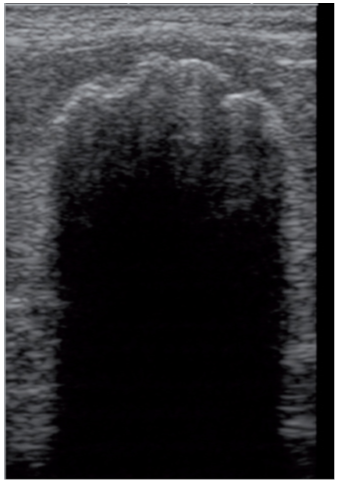

某些临床操作,例如镇静和麻醉,会使脾脏的大小及超声表现发生改变。一项研究评估了使用七氟烷和献血之后,脾脏的形态改变。全身麻醉后的脾脏比正常脾脏的高度明显增加,献血之后脾脏高度明显降低。但从临床角度来看,这样的差别可能没有很大的临床意义。